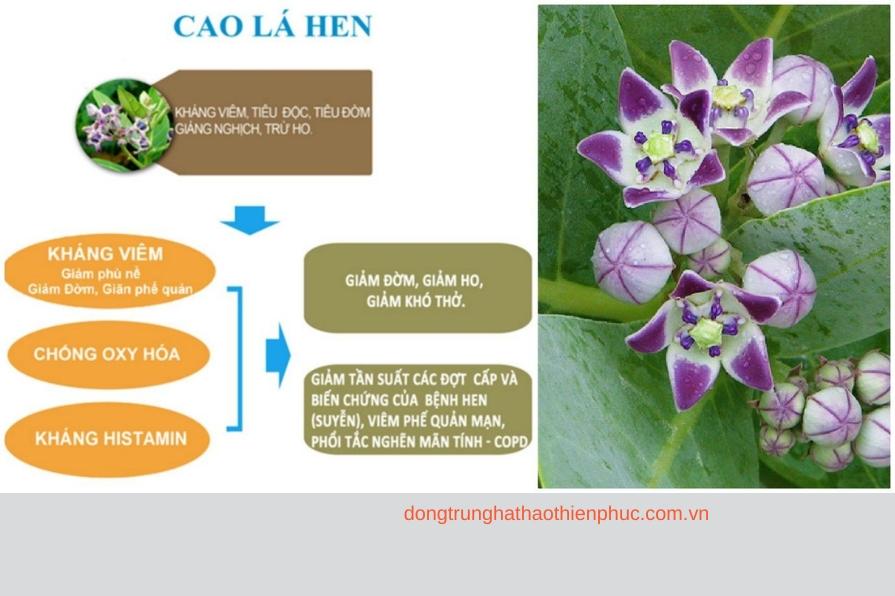

2. Hỗ Trợ Sức Khỏe Phổi

Cordyceps Sinensis được biết đến với khả năng hỗ trợ sức khỏe phổi, giúp cải thiện hô hấp và giảm các triệu chứng liên quan đến bệnh về đường hô hấp như hen suyễn và viêm phế quản. Loại dược liệu này giúp làm sạch phổi, tăng cường lưu lượng oxy trong máu, từ đó giúp cơ thể khỏe mạnh hơn.

- Cordyceps Sinensis cho sức khỏe phổi: Đặc biệt, những người hút thuốc hoặc sống trong môi trường ô nhiễm có thể hưởng lợi từ tác dụng thanh lọc phổi của Cordyceps Sinensis.